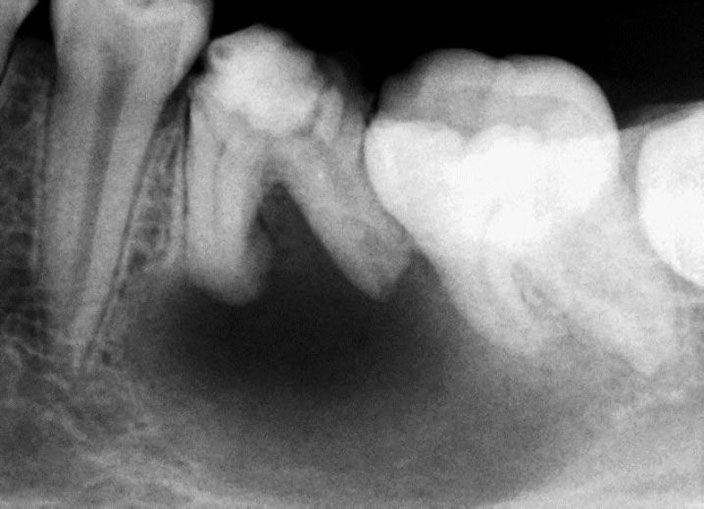

Pre-op

Pain in mandibular first molar after endo. Previous dentist unable to locate mesial canals. Obturated only the distal canal. Patient has generalized periodontal problems as well.

Pre-op, EDTA for 1 minute, After 1 minute EDTA

Red arrows show the two “white spots” indicating the calcified mesial canals.

Missed second distal canal (red arrow)

Pre-op & Post-op